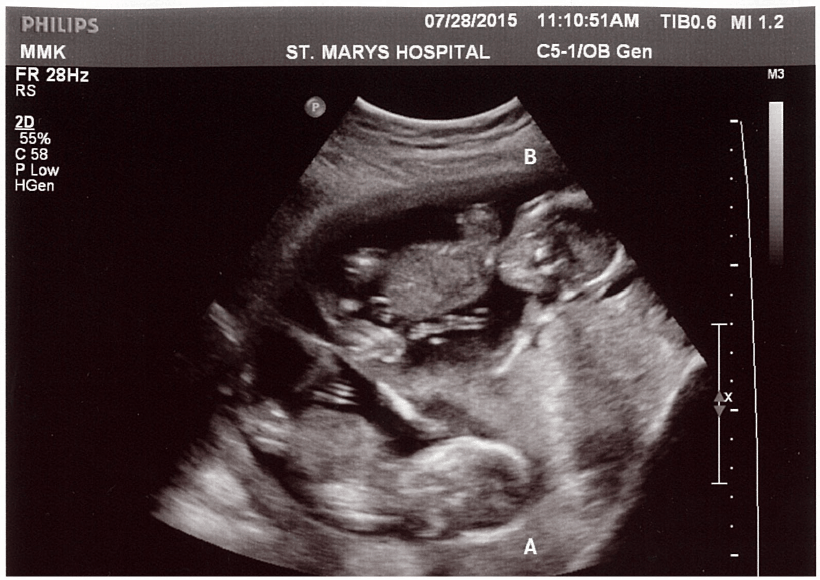

Ultrasound Photos at 15 Weeks Pregnant With Twins